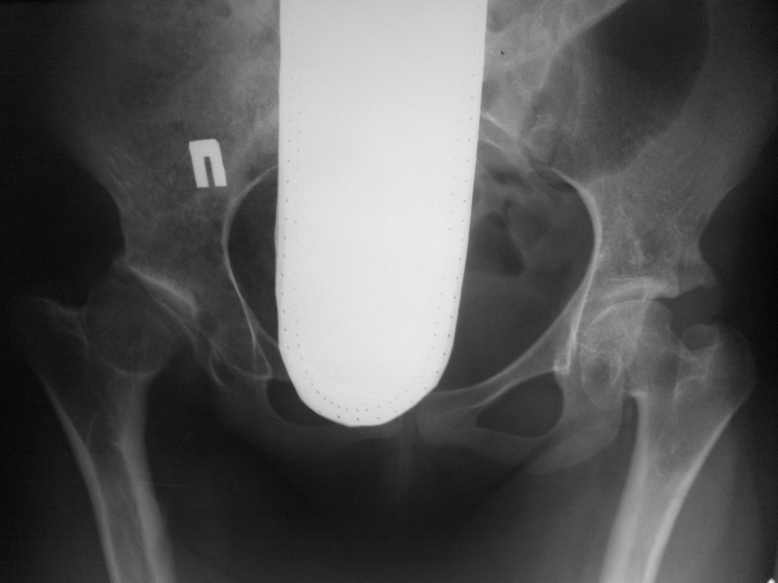

Обратилась девушка 16-ти лет с жалобами на боли в правом тазобедренном суставе

Здравствуйте уважаемые коллеги, Обратилась девушка 16-ти лет с жалобами на боли в правом

тазобедренном суставе. С анамнеза известно; у пациентки легкая форма ДЦП , в возрасте 5-ти

лет ребенок был прооперирован по поводу врожденного вывиха бедер. Клинически ; движения в

правом суставе ограничены( сгибание 80,отведение 25, ротация 10-0-5.) Посоветуйте

тактику лечения. С уважением Ihor.